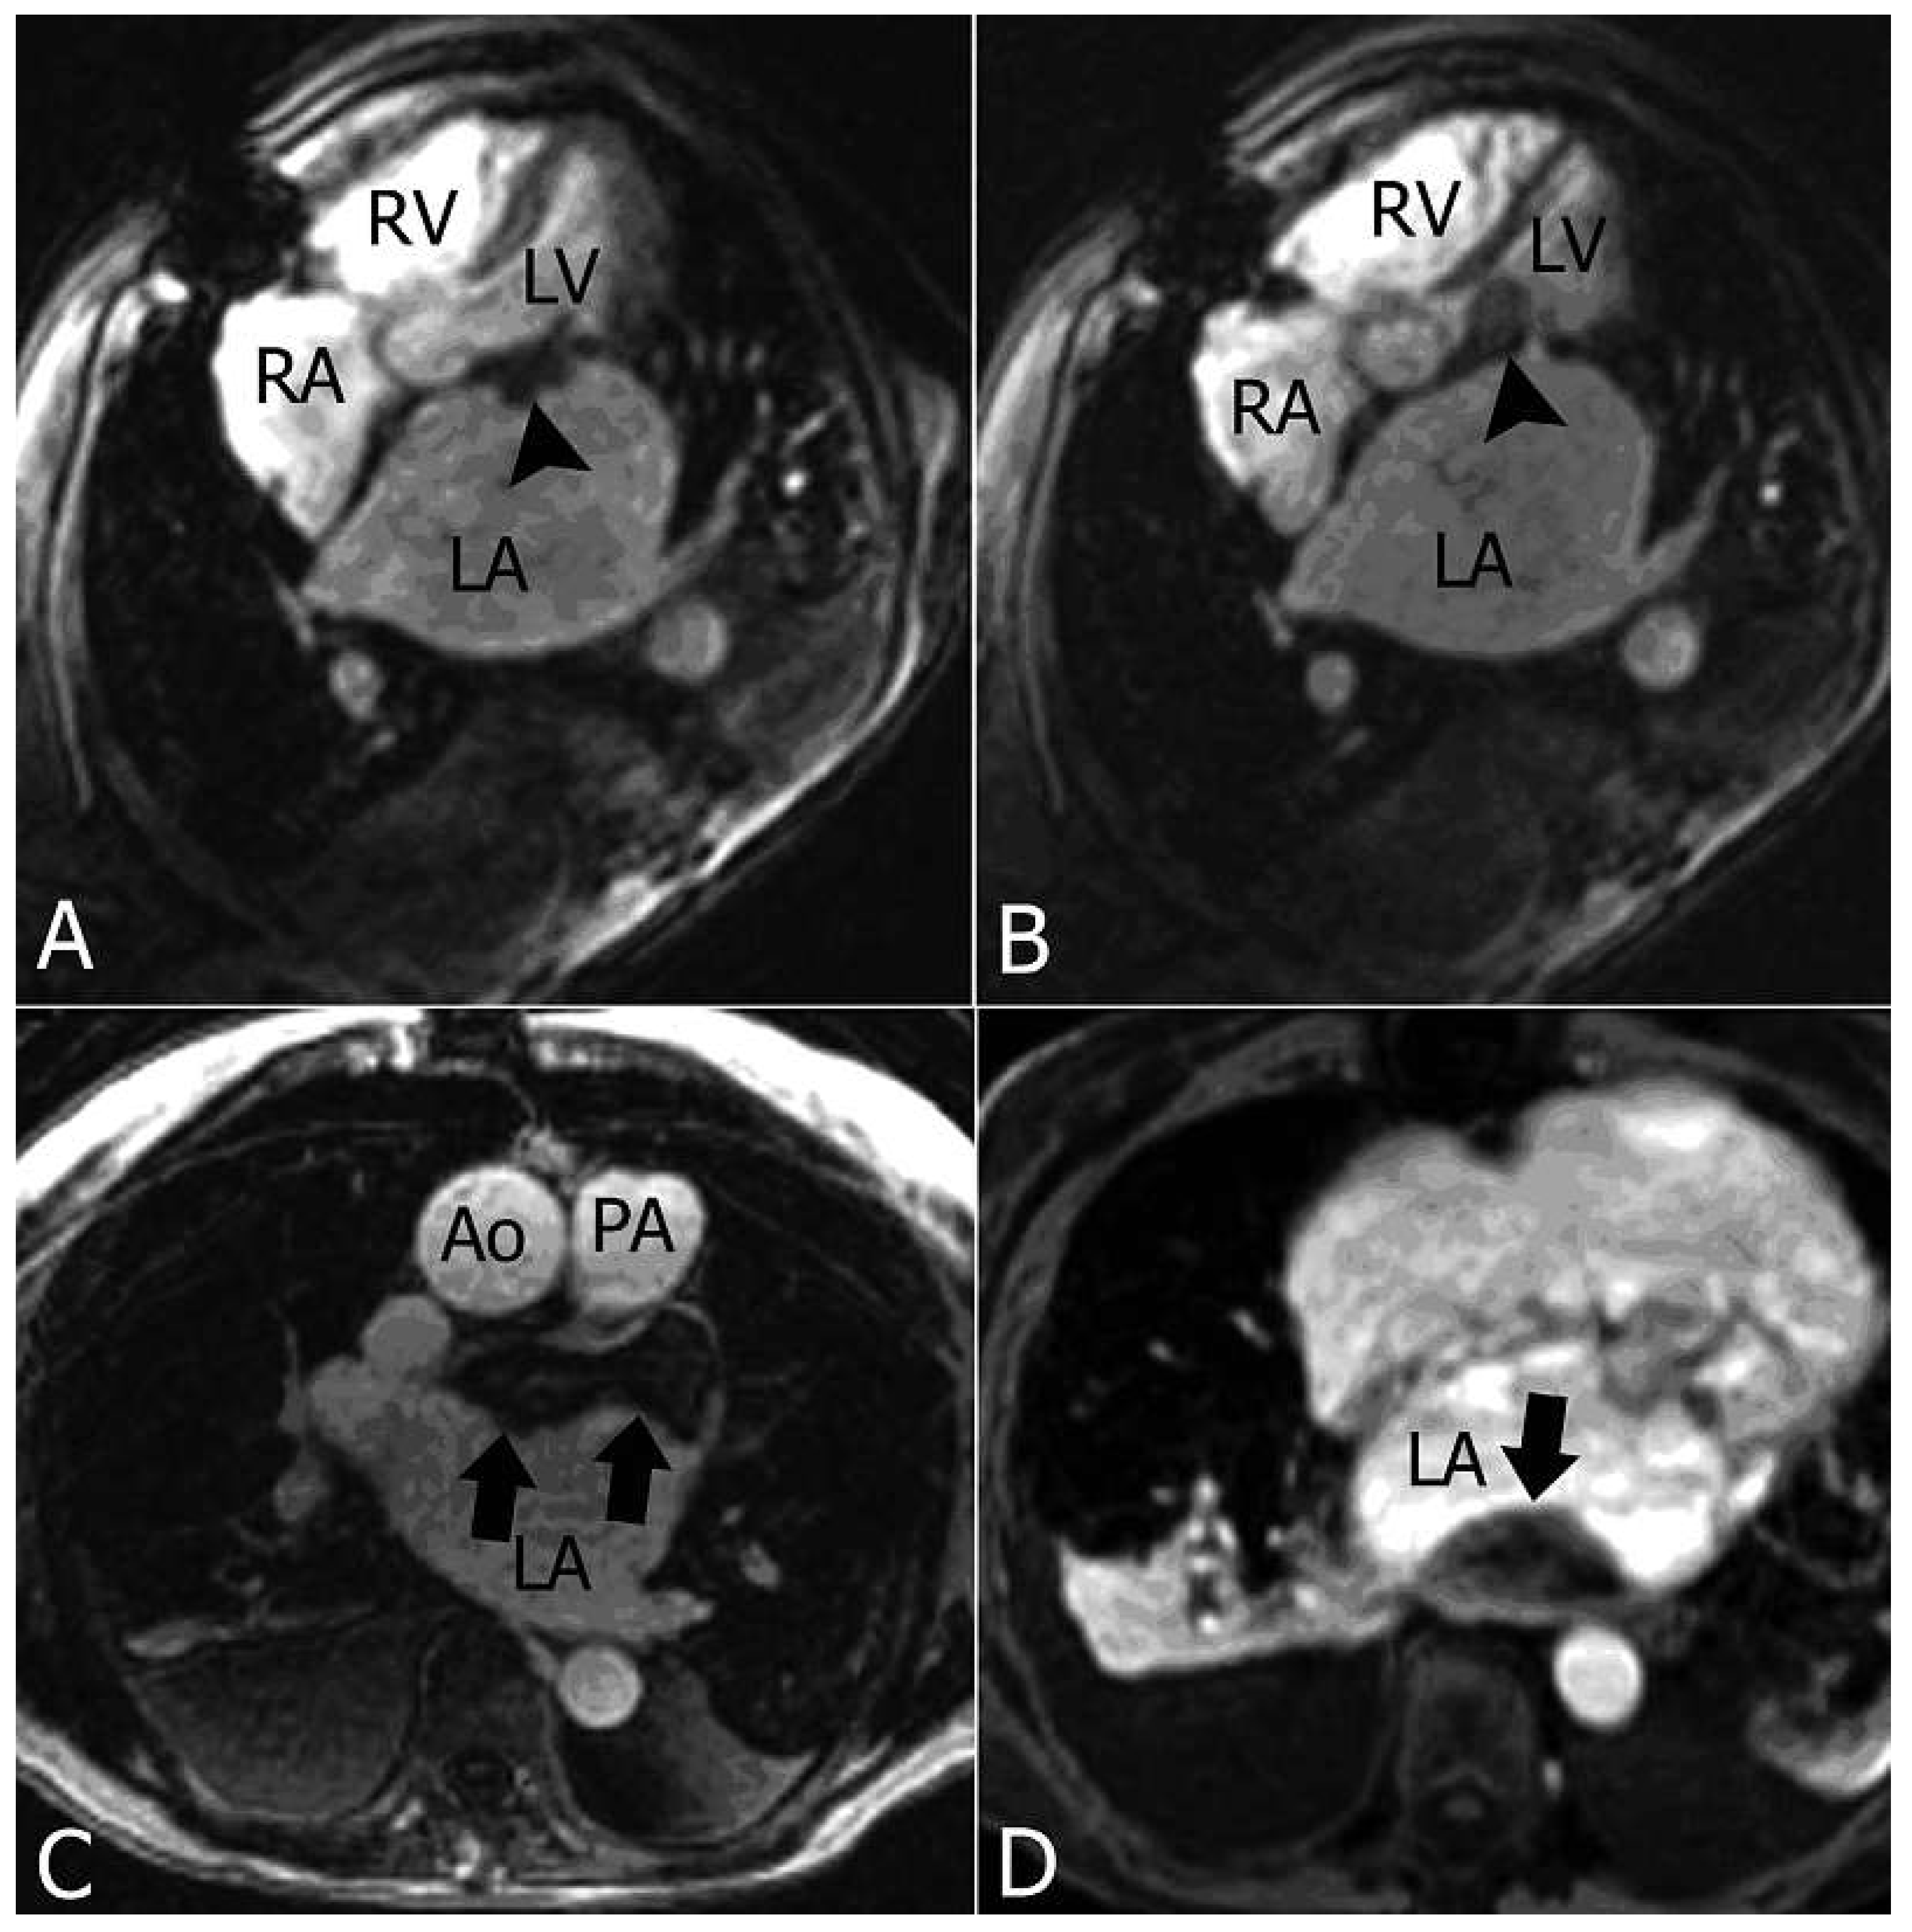

Cardiac MR confirmed the findings (Figure 2).

Figure 2. The axial MR images show enlargement of LA, confirming the presence of a solid lesion on the free edge of the anterior mitral leaflet (arrowhead in A and B) and the solid tissue occluding the left appendage and extended along the anterior wall and roof of the LA (arrows in C), associated with a similar finding along the posterior LA wall (arrow in D). Ao = aorta; LA = left atrium; LV = left ventricle; PA = pulmonary artery; RA = right atrium; RV = right ventricle.